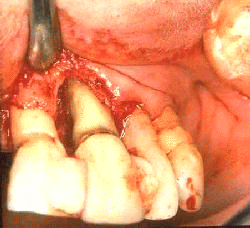

La anatomía macroscópica de la destrucción periodontal en la superficie mesio-bucal del central superior derecho. El colgajo  levantado hasta la línea mucogingival descubre un gran defecto óseo. En la superficie  mesial el defecto incluye una destrucción infraósea con la permanencia de una pared ósea. En la superficie bucal del diente el defecto intraóseo  es  poco profundo  alrededor de 1 mm de profudidad. La superficie de la raíz  bucal y los sitios de  mesial son desiguales con  numerosos hoyos y surcos. Estos defectos anatómicos probablemente han contribuido al modelo de colonización  bacteriana  subgingival y han determinado el modelo de destrucción ósea.